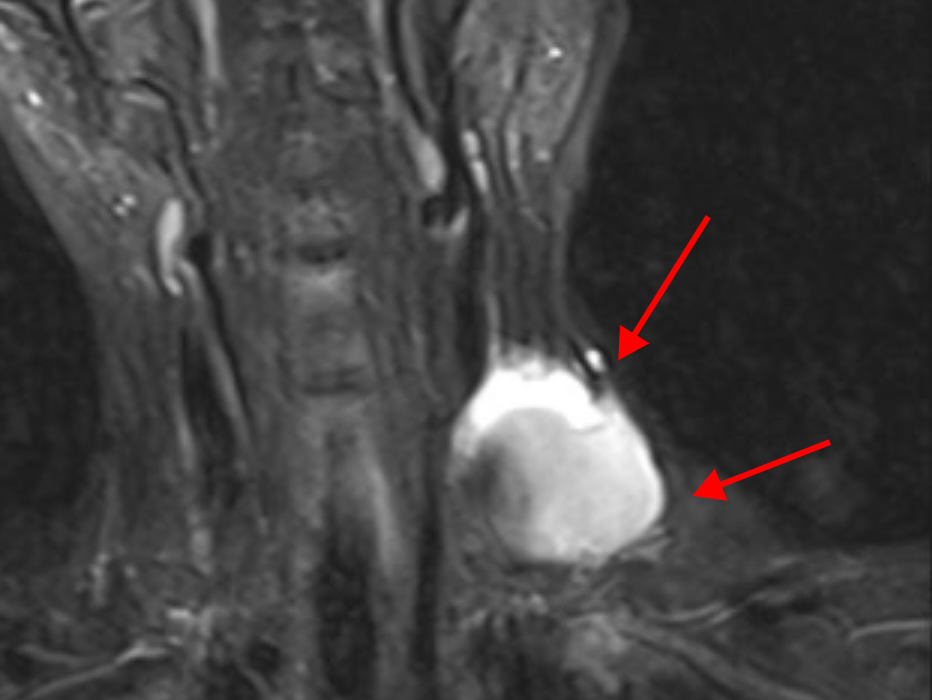

医生经过询问病史,以及细致的检查后,明确诊断为左颈内静脉假性动脉瘤,而且文女士的静脉瘤体巨大,最大直径达到7厘米,一旦破裂就会有生命危险!

除了瘤体巨大,还有大量血栓,瘤体破口的长度约2厘米,还存在血栓脱落导致肺栓塞的风险,加之文女士还有缺铁性贫血等情况,病情极为复杂。

文女士发生病变的颈静脉部分,是人体头部血液回流心脏的通路,主要作用就是调节血管系统容量。